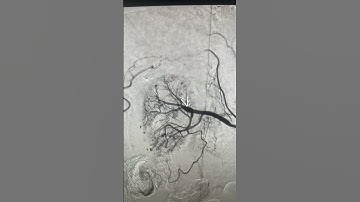

Renal Pseudo-aneurysm Embolization